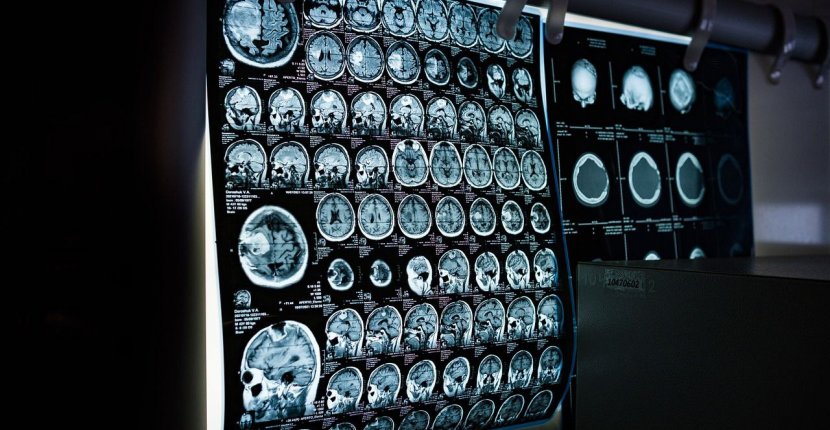

Ученые РЭУ им. Г. В. Плеханова и НМХЦ им. Н. И. Пирогова разработали новый метод «объяснимого» искусственного интеллекта для анализа электроэнцефалограмм (ЭЭГ). Предложенная технология не только автоматически выявляет эпилептические приступы с высокой точностью, но и прозрачно объясняет свои решения, указывая, какие именно участки мозга и частотные диапазоны стали решающими для постановки диагноза.

Разработка решает проблему «черного ящика». Интерпретируемость ИИ адаптировали под специфику исследования (электроэнцефалографии): метод комбинирует анализ частотных диапазонов и пространственное картирование мозга. Ведущий научный сотрудник НИИ прикладного искусственного интеллекта и цифровых решений РЭУ им. Г. В. Плеханова Вадим Грубов рассказал:

Врачам важно не просто получить вероятность приступа, но и увидеть, почему модель приняла такое решение. Наш фреймворк позволяет визуализировать эти признаки в виде тепловых карт, где отмечены конкретные зоны коры головного мозга и спектральные паттерны. Это переводит работу ИИ с языка математики на язык нейрофизиологии.